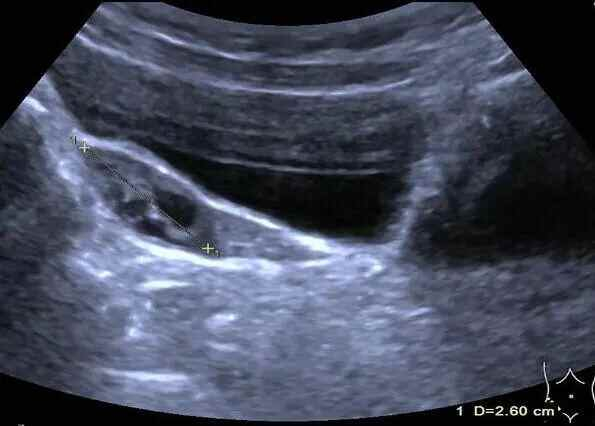

▲彩超下,婷婷的双侧卵巢内见8个直径大于4mm卵泡

▲左侧卵巢体积约4.9ml,内见4个直径大于4mm卵泡

▲右侧卵巢体积约3.2ml,内见4个直径大于4mm卵泡